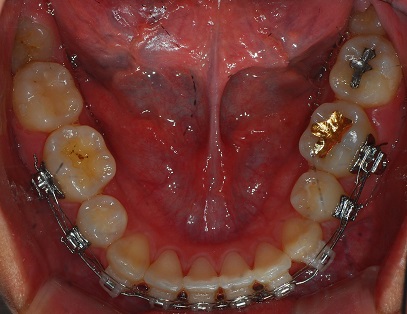

하악 사진